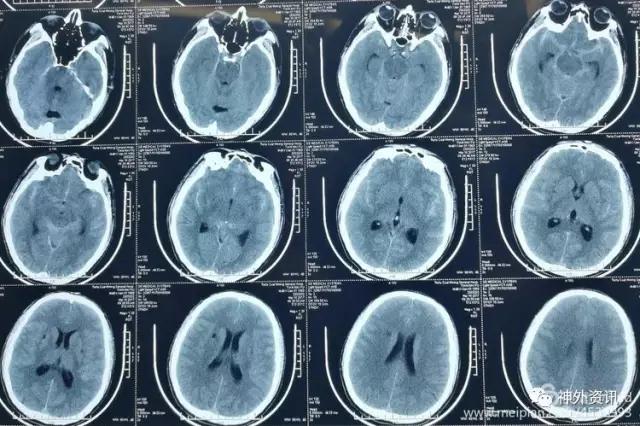

男,46岁,突发头痛2小时入院。既往否认有高血压病。入院时神志清,问答正确,瞳孔及肢体活动正常,颈强直(+)。

CT平扫提示SAH,鞍上池和双侧外侧裂池广泛均匀分布。